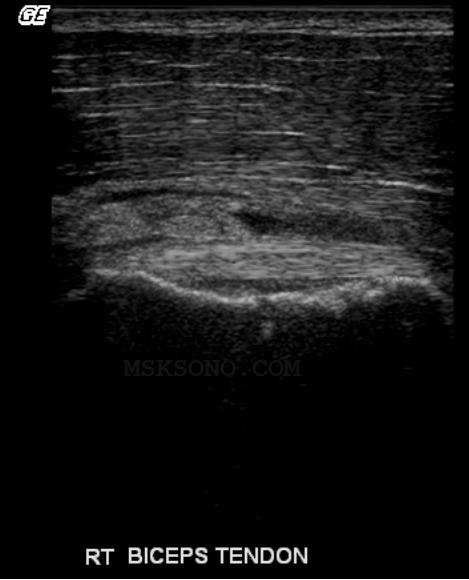

Bicep tendon

resting in the

footprint of the

Subscapularis

Tendon region